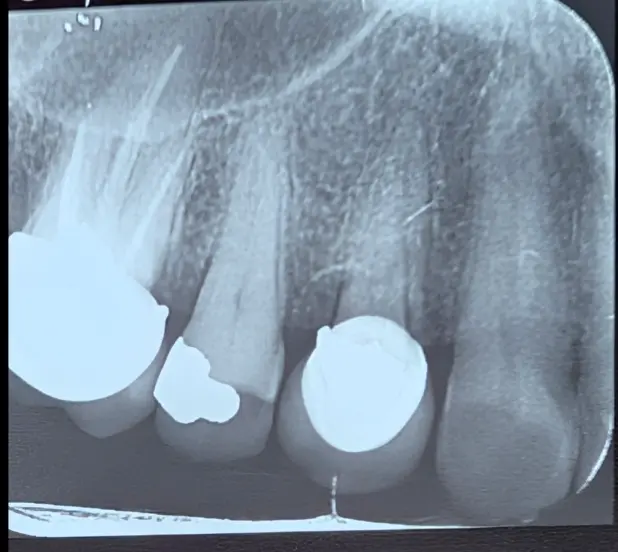

در این کیس، بیمار با شکایت از درد شدید سمت راست فک بالا مراجعه کرد. بیمار و حتی نمای ظاهری دندان‌ها (سایش شدید دندان ۵) انگشت اتهام را به سمت دندان پرمولر دوم می‌بردند، اما حقیقت چیز دیگری بود.

نتایج تست‌ها نشان داد که دندان ۵ با وجود سایش، مشکل پالپی ندارد و عامل اصلی درد، دندان ۴ است که به‌تازگی روکش شده.

نکته کلیدی: در دردهای شدید، پدیده "درد ارجاعی" می‌تواند هم بیمار و هم دندانپزشک را گمراه کند. تنها تست‌های دقیق اندو می‌تواند مجرم واقعی را از دندان‌های کناری تمیز دهد.